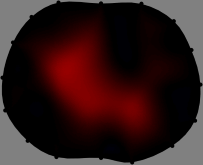

Figs. 3 and 4 compare the performance of the proposed FER method in (20) with the standard regularized least-squares method ((19) when \mathcal{R} is the identity matrix). The regularization parameter of the standard method was heuristically chosen for its best performance, and the parameter of the FER method was set to be one of three different values λ=0.05,0.2,𝜆0.050.2\lambda=0.05,0.2,\infty. The injection current was 1 mARMSRMS{}_{\tiny{\mbox{RMS}}} at 100 kHz, and the frame rate was 9 frames per second. The reference frame at t0subscript𝑡0t_{0} was obtained from the maximum expiration state. The measured data, 𝐕˙(tm)˙𝐕subscript𝑡𝑚\dot{\mathbf{V}}(t_{m}), represent the voltage differences between each time tmsubscript𝑡𝑚t_{m} and t0subscript𝑡0t_{0}. The blue regions, which denote where conductivity decreased by inhaled air, increased during inspiration and decreased during expiration. The FER method with λ=𝜆\lambda=\infty was clearly more robust than the standard method that produced more artifacts originated from the inversion process.

Figure 3: The reconstructed images of the conductivity change of the subject A by the standard regularized least square method and the proposed fidelity-embedded regularization (FER) method for three difference values λ=0.05,0.2,𝜆0.050.2\lambda=0.05,0.2,\infty. Here, the time step is 0.22 seconds (tm+2tm0.22subscript𝑡𝑚2subscript𝑡𝑚0.22t_{m+2}-t_{m}\approx 0.22).